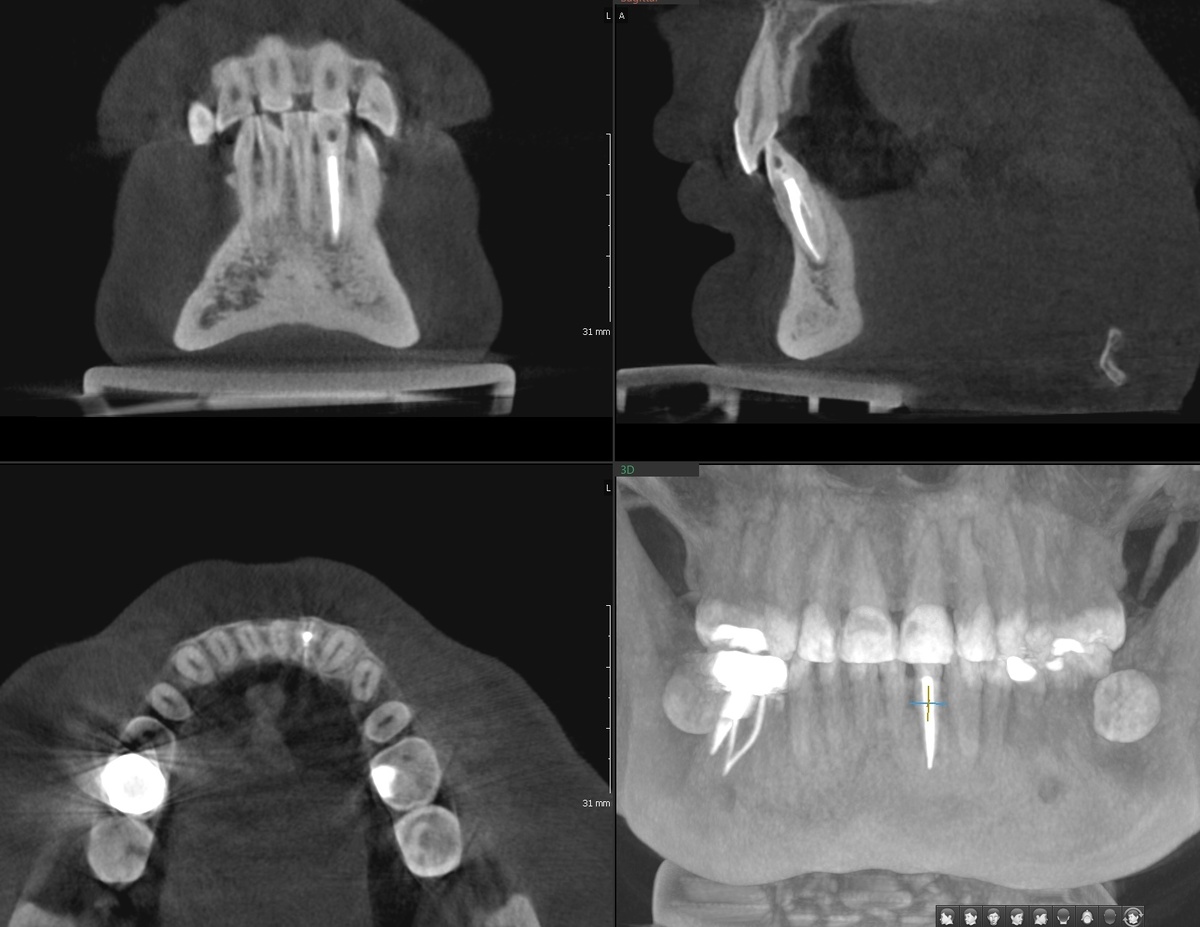

И да, вот что обнаружилось на снимке:

Периодонтит зуба 3.2

Признаки почившего много лет назад (2014 год, если память не изменяет) зуба. 8 лет в кости был очаг деструкции.